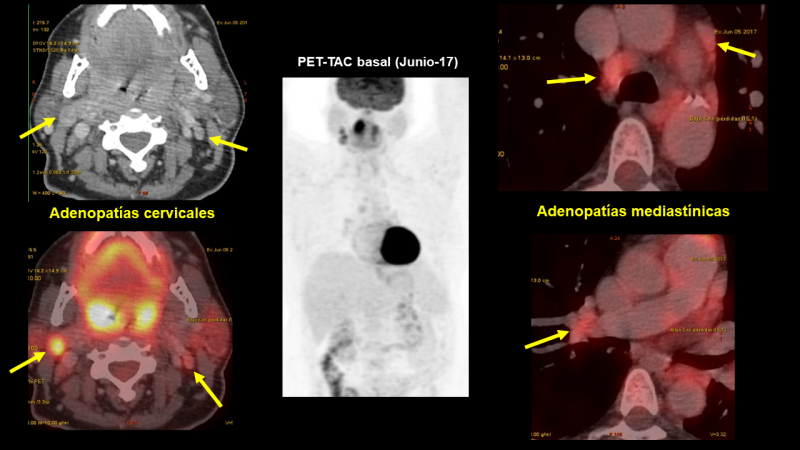

Un estudio PET-CT con FDG muestra (figs. 1 y 2):

Lesión en nasofaringe con incremento de actividad metabólica (SUV 7,4), con una lesión seudonodular en la porción central, de 16 x 11 mm.

Lesión en amígdala palatina derecha, de aproximadamente 23 x 24 mm. Ambas amígdalas presentan un aumento de captación de FDG, a predominio derecho (SUV 15-17).

Adenopatías con incremento de la actividad metabólica en las siguientes localizaciones:

Nivel II A derecho (SUV 10) de 18 x 23 mm.

Nivel II B izquierdo (SUV 3,2) de 11 x 4,6 mm.

Paratraqueal inferior derecha (SUV 5) de 12,7 x 10, mm.

Prevasculares (SUV 3.2) de 15 x 7 mm

Hiliar derecha (SUV 3,4) de 16 x 12 mm.